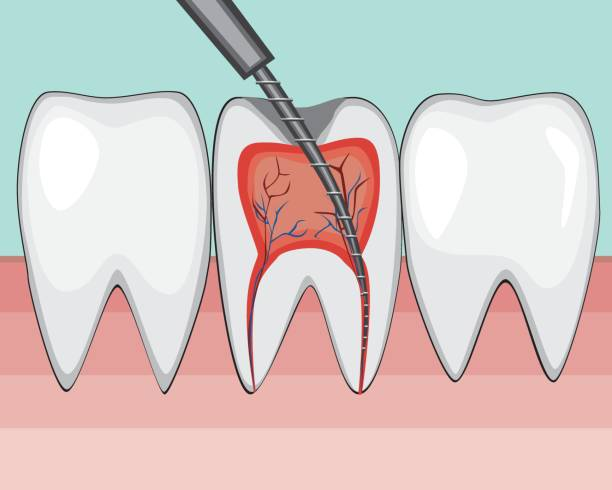

深圳牙科杜牙根只需500蚊?北上睇牙新選擇?深圳維港口腔口腔牙醫為你解答:我哋維港口腔嘅杜牙根治療價格因牙齒位置同治療複雜程度有所唔同。

根據2025年最新嘅收費標準:成人前牙杜牙根治療嘅價格為680蚊/隻,後牙杜牙根治療價格為500蚊/根。兒童治療嘅價格為1200蚊,顯微/複難根管治療會加收50%嘅費用。

深圳維港口腔系一間正規嘅私立牙科單位,其杜牙根治療價格在同類單位中具有一定嘅性價比。例:前牙根管治療價格在680蚊/隻,屬於當地較中等水準。此外,我哋維港口腔還提供杜牙根治療套餐,包括補牙同瓷牙修復,價格透明且實惠。

選擇深圳維港口腔進行根管治療,唔僅價格合理,還能享受到專業、貼心嘅服務。各分院有經驗豐富嘅醫生團隊,醫生均畢業於國內頂尖口腔醫療大學,個人具備豐富嘅臨床經驗。此外,醫院配備先進嘅根管治療設備,確保治療嘅精准性同舒適性。